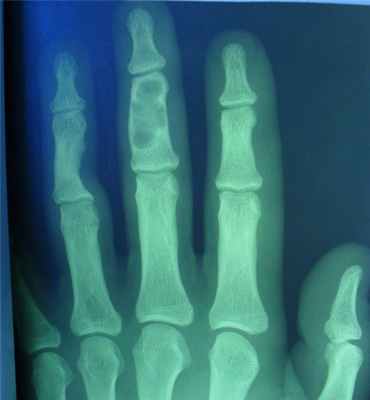

27. Энхондромы – внутрикостные опухоли из зрелого гиалинового хряща

• Возраст – 20-40 лет

• Локализация – короткие трубчатые кости,

чаще всего метадиафизы

• Дифференциальная диагностикахондросаркомы

28. Рентгенсемиотика

• Очаги деструкции,

центральные,

эксцентиричные,

субпериостальные

• Вздутие с

истончением

замыкающей

пластинки

• Могут содержать

обызвествления

• Кортикальный слой

истончен изнутри

- поражаются фаланги, пястные, плюсневые, реже запястные кости, отростки позвонков, передние концы верхних ребер, тазовый скелет, грудина и весьма редко – длинные трубчатые периферические кости,

- в малых цилиндрических костях хондромы гнездятся в диафизах и эпифизах, в больших трубчатых – только в метафизарных костях,

- как правило хрящевые опухоли множественны и чаще всего наблюдаются в числе одного или нескольких на фалангах рук и пястных костях,

- чаще процесс двусторонний, но не симметричный.

- опухоли шарообразны или овальны, расположены то центрально и вздувают кость изнутри, то эксцентрично и более поверхностно и связаны только с корковым веществом кости,

- опухоль состоит из прозрачного, хрящевого фона на котором видны островки, точечки из извести или костного вещества,

- наружные контуры гладкие и при доброкачественном течении не прерываются,

- на месте слияния опухолевых шаров костная перегородка иногда толстая, в других случаях истончена или отсутствует,

- при поражении эпифизарных хрящей приходится видеть торможение роста кости в длину или ее искривлении,

- нередко центрально расположенная хондрома осложняется патологическим переломом,

- корковый слой неравномерен и местами утолщен,

- при хондроме поверхность кости шероховата.